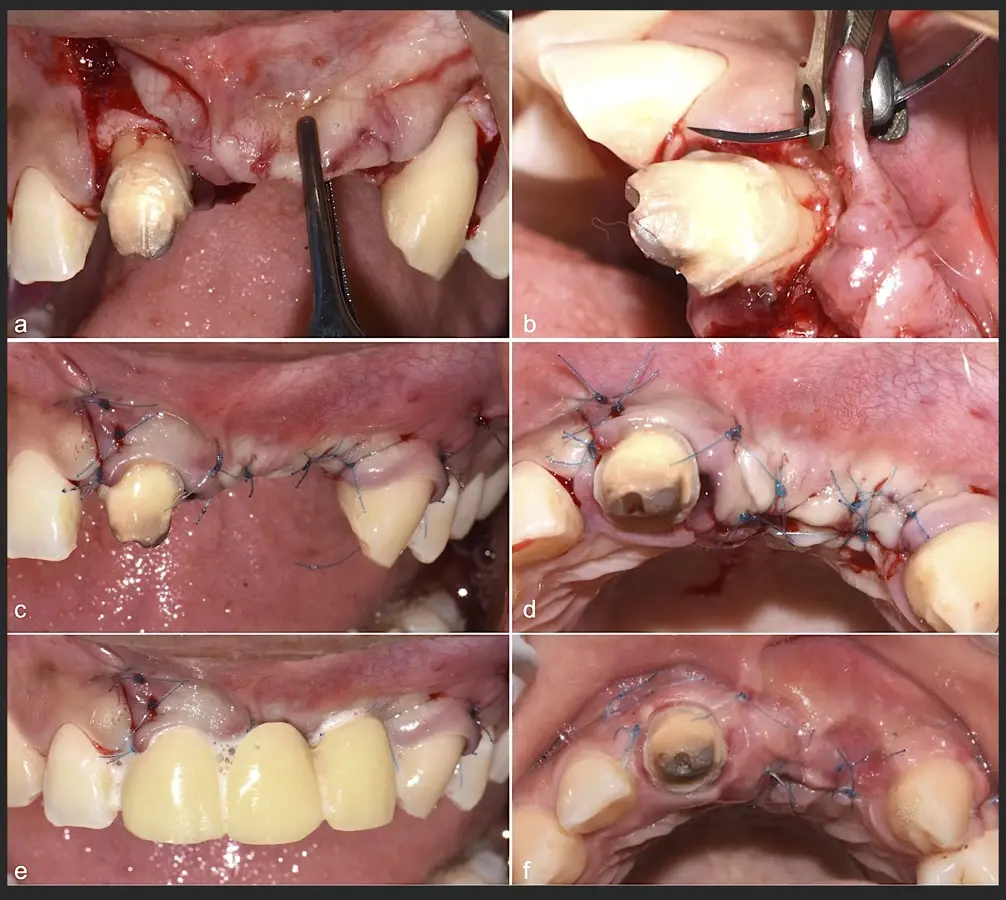

Figura 44. Pasos para la colocación de la membrana de barrera (a - d).

Figura 45. Afrontamiento de colgajo y sutura (a - e). Control a los 7 días postquirúrgico (f).

Figura 46. Control a los 10 días post cirugía.